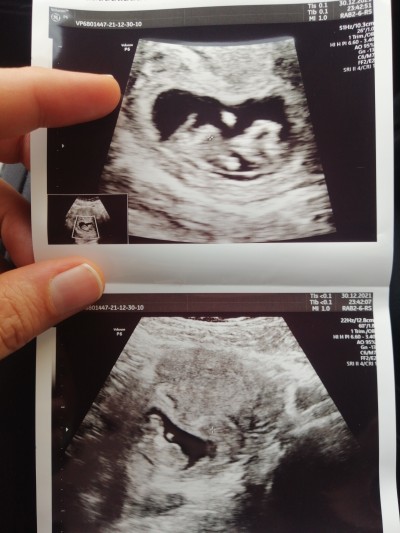

Bu post eda güneş için açılmıştır cinsiyet tahmini :D

hade kurban senin için post açtım bursa kalacak

Askom bas bas bagriyo erkegim ben diye :DD

Kız istediğin haber vermek olsun annemden bacımdan önce sana haber vericem söz veriyorum canısı :D

Hahahaha benimkinin pipisi kısa bacım :D